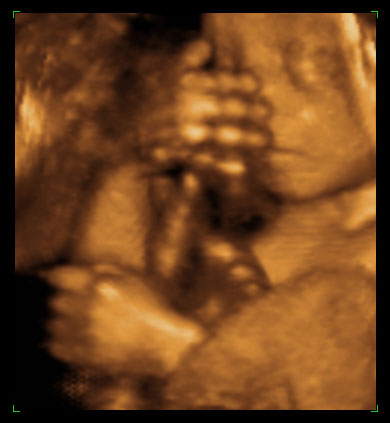

ултразвучни приказ бебе 24. недеље трудноће (1)

ултразвучни приказ бебе 24. недеље трудноће (2)

ултразвучни приказ бебе 24. недеље трудноће (3)